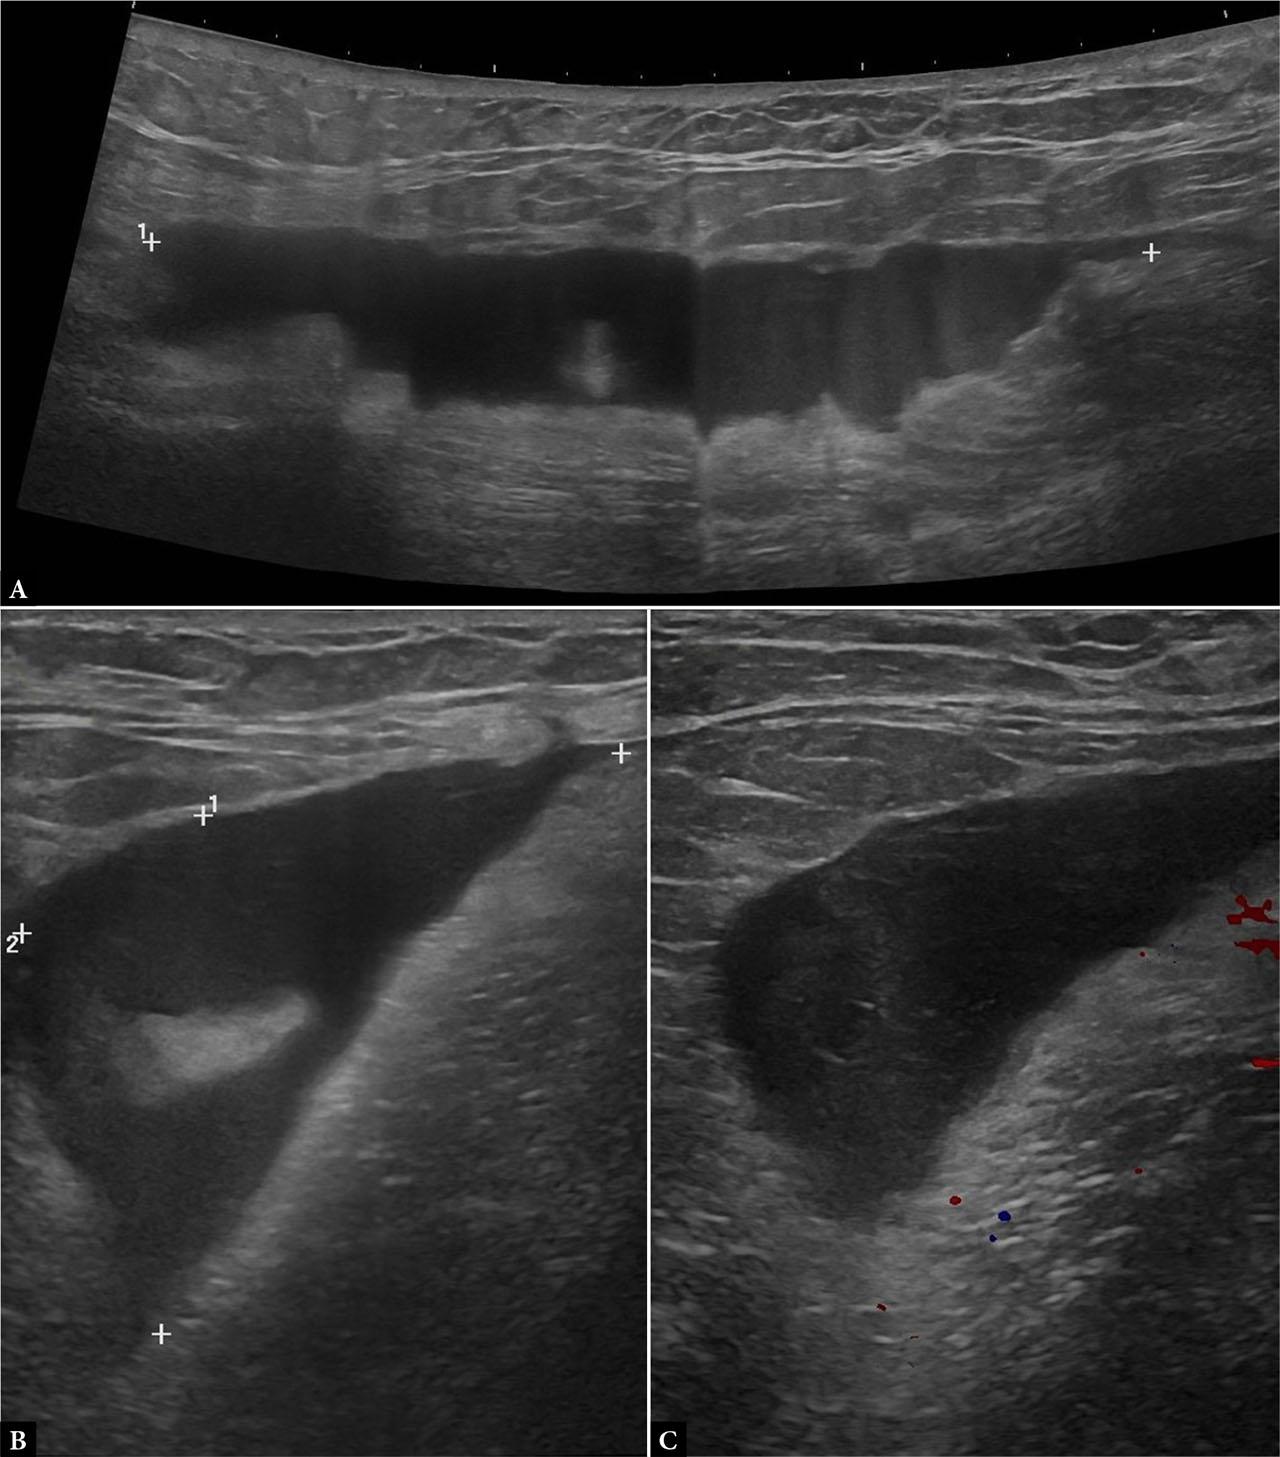

A US examination of the abdominal wall was performed to characterize the swelling. Sonography identified two fluid collections, one anechoic and homogeneous, suggestive of a seroma, and one on the left, more inhomogeneous, consistent with a hematoma. No internal vascularity was noted within either collection on CD imaging (Fig. 7). Postoperative fluid collections represent common complications following abdominoplasty, particularly when combined with bariatric procedures.

Ultrasound of the abdominal wall demonstrating a right-sided anechoic subcutaneous collection consistent with a postoperative seroma (A) and a left-sided collection with internal echogenic strands and particulate content consistent with a hematoma (B)